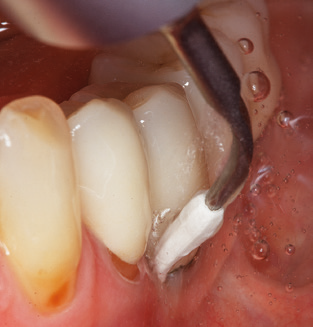

Dopo la pulizia meccanica delle superfici dei denti e degli impianti, le superfici dei denti naturali vengono pulite manualmente utilizzando strumenti manuali standard. Quando si esegue la pulizia manuale, è necessario prestare particolare attenzione a mantenere il corretto angolo di applicazione, un'adeguata nitidezza, un buon supporto e lavorare con la curette dall'apicale al coronale. Curette in titanio o carbonio devono essere utilizzate per la post-pulizia delle strutture dell'impianto (Fig. 8). Oltre all'uso di dispositivi ad ultrasuoni, i dispositivi power jet possono essere utilizzati anche in odontoiatria conservativa. Tuttavia, si deve considerare che queste procedure non sono adatte per rimuovere depositi duri e quindi non possono sostituire completamente l'uso di strumenti manuali e strumenti ad ultrasuoni. In tutti i casi, la pulizia è seguita dalla lucidatura meccanica del dente accessibile e delle superfici dell'impianto con ventose e composti di lucidatura (Fig. 9).

Fig. 4: Sonde flessibili con marcature millimetriche sono consigliate per il sondaggio di impianti dentali (ad es. Colorvue Kit PCV11KIT6, HuFriedy). - Fig. 5a e b: Un inserto diritto (1P, W&H Dentalwerk Bürmoos GmbH) è uno strumento adatto per l'uso su tutti i denti naturali. - Fig. 6: Inserti curvi (3Pr / 3Pl, W&H Dentalwerk Bürmoos GmbH) si prestano alla lavorazione di aree difficili da raggiungere del dente e delle superfici radicolari (ad es. Forcazioni). - Fig. 7: L'inserto esagonale conico per la pulizia dell'impianto (1I, W&H Dentalwerk Bürmoos GmbH) consente una pulizia atraumatica ed efficace della superficie della corona e del moncone. - Fig. 8: Le curette in titanio e carbonio sono strumenti adatti per la pulizia manuale delle superfici dell'impianto.